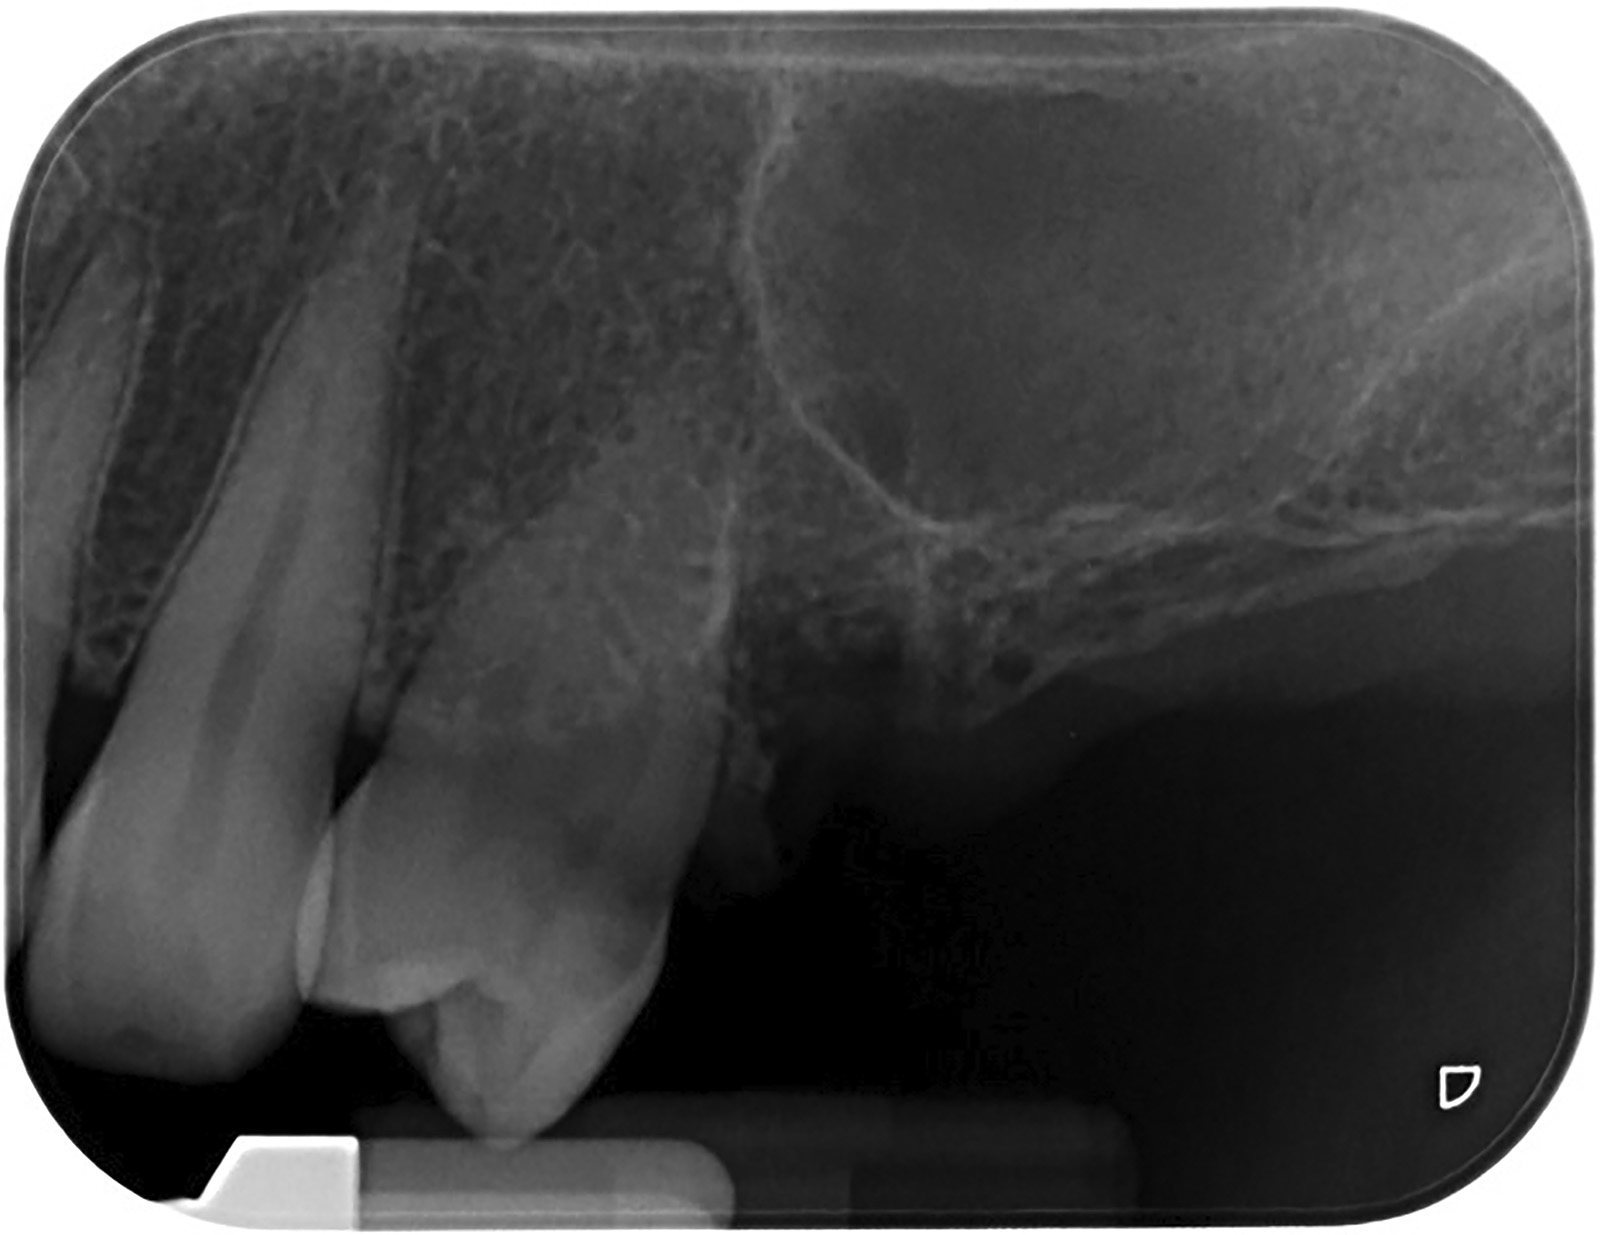

PREMESSA: in seguito all’estrazione dell’incisivo laterale superiore di destra, resasi necessaria per cause batteriche, si decide di affrontare il caso con il posizionamento di un impianto in sostituzione dell’elemento mancante dopo guarigione del sito infetto. Con tecniche rigenerative sia dei tessuti ossei mancanti a causa dell’infezione pregressa, sia dei tessuti gengivali che appaiono inizialmente troppo spostati in alto, si ripristina una corretta morfologia delle parabole (contorni) gengivali e delle papille interdentali (triangoli di gengiva tra due denti vicini).